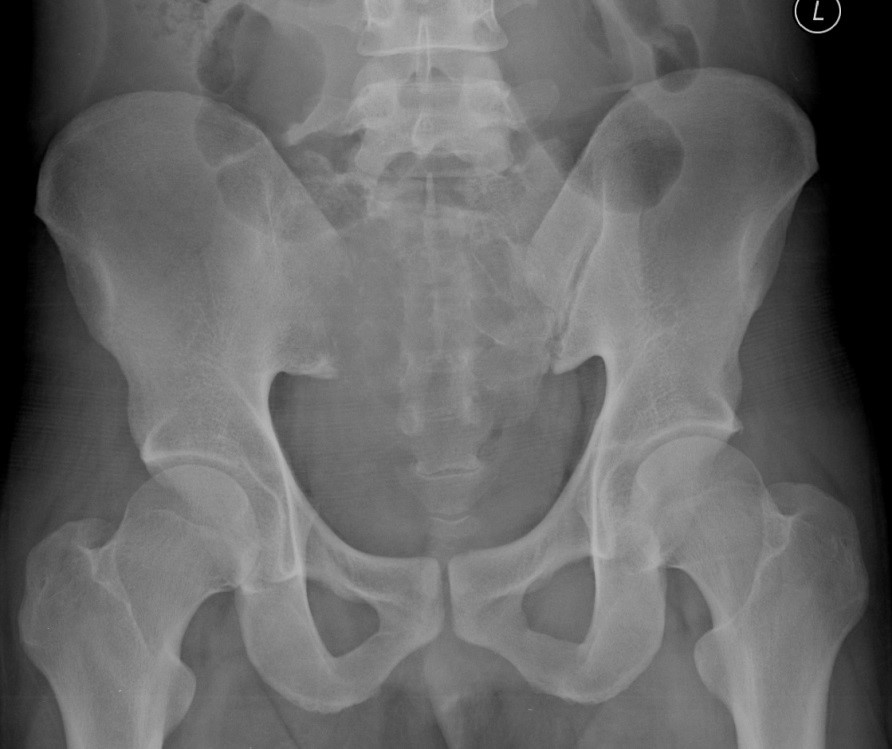

Primary lymphoma of the sacral bone is a rare myeloproliferative disease, occurring mostly after 4th decade of life and mainly in male patients. We reported a case of sacral bone lymphoma in a 24-year-old man with low back pain and radiculopathy. Imaging showed a sacral bone lesion which later proved to be non-Hodgkin’s lymphoma on histopathologic study. Lymphoma of the sacral bone is chemoresponsive and carries a good prognosis. Sacral bone lymphoma should be considered as a differential diagnosis in patients with low back pain who is not responding to analgesic treatment.